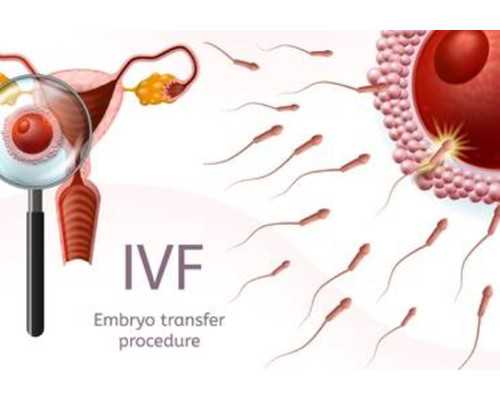

煙臺山醫院的試管嬰兒費用通常在3-8萬元之間。具體包括術前檢查、促排卵、胚胎培養及移植等環節。例如,術前檢查費用約為4500-9000元,促排卵藥物費用約為1-2萬元,手術及胚胎移植費用約為1-2萬元,總費用可能達到3萬元左右。但現如今煙臺山醫院試管可報銷,其自費的開銷變少。即,煙臺山醫院提供的試管嬰兒輔助生殖技術的醫保報銷比例大約為50%。報銷時,患者準備相關的門診病歷、輔助檢查單、門診慢病認定申請單以及夫婦雙方的身份證和結婚證等材料,到窗口報銷即可。

4、冷凍胚胎二次移植費用低

有無冷凍胚胎。假如夫妻做完一次移植后還有多余胚胎,能夠冷藏備用,要求交納胚胎冷凍保管費。假如要進行凍胚移植還需交納冷凍胚胎的復蘇費用。